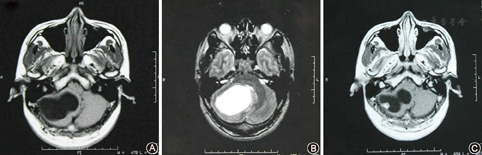

头颅MRI检查:小脑血管母细胞瘤术前MRI检查(1997年8月,图1)示右侧小脑半球见一椭圆形囊性病灶,大小约5.5 cm×4.0 cm,囊壁内见一直径约1.0 cm壁结节,增强扫描壁结节强化明显,大囊未见强化,囊壁清晰。术后MRI(2009年12月,图2)检查示右侧小脑血管母细胞瘤术后改变,右侧枕叶小片陈旧性软化灶,局部小脑内片状异常信号影,边界不清,信号欠均匀, T1WⅠ为低信号,T2WⅠ为高信号,增强未见明显异常强化,未见肿瘤残留或复发。

A.T1像右侧小脑半球见一椭圆形囊性病灶,大小约5.5 cm×4.0 cm;B.T2像四脑室受压,囊内信号均匀;C.增强扫描囊壁内见一大小约10 mm壁结节,强化明显,大囊未见强化,囊壁清晰